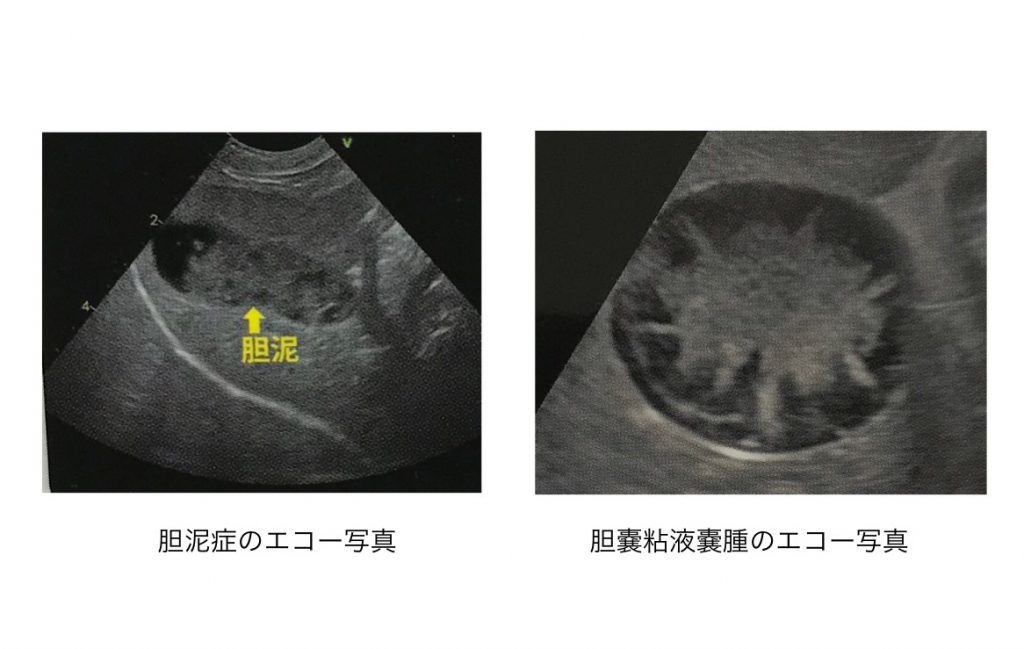

胆泥症は無症状で経過することが多いため、定期的な健康診断で早期発見を心がけましょう。 また、胆嚢炎や内分泌疾患( 甲状腺機能低下症 や 副腎皮質機能亢進症 )などのような、

犬 胆泥症 原因-胆泥 をかたちづくっているのは コレステロール や 黄疸色素 ( ビリルビン )、 カルシウム などの微細な 結晶 が 胆嚢壁 から分泌される 粘液 に包まれたものと考えられますが、他にも 炎症 によっこんにちは。獣医師の清水いと世です。 今回は、わんちゃんの胆泥症について説明します。 前編は、胆泥症の原因や検査方法や症状について、後編は治療や予防方法について説明します。 犬の胆泥

胆泥症・胆石症について 胆嚢は、胆汁を産生し貯留する器官です。 胆汁には、脂肪を分解し水に溶けやすい状態に(乳化)する役割を持っています。 胆嚢に貯えられた胆汁は、元々サラサラの水胆泥を生じさせた原因や疑われる原因があれば、それを取り除きます。 そのために、 犬の胆泥症 <前編> で説明した原因追及のための検査結果が重要になります。 肝臓の異常が認められるので